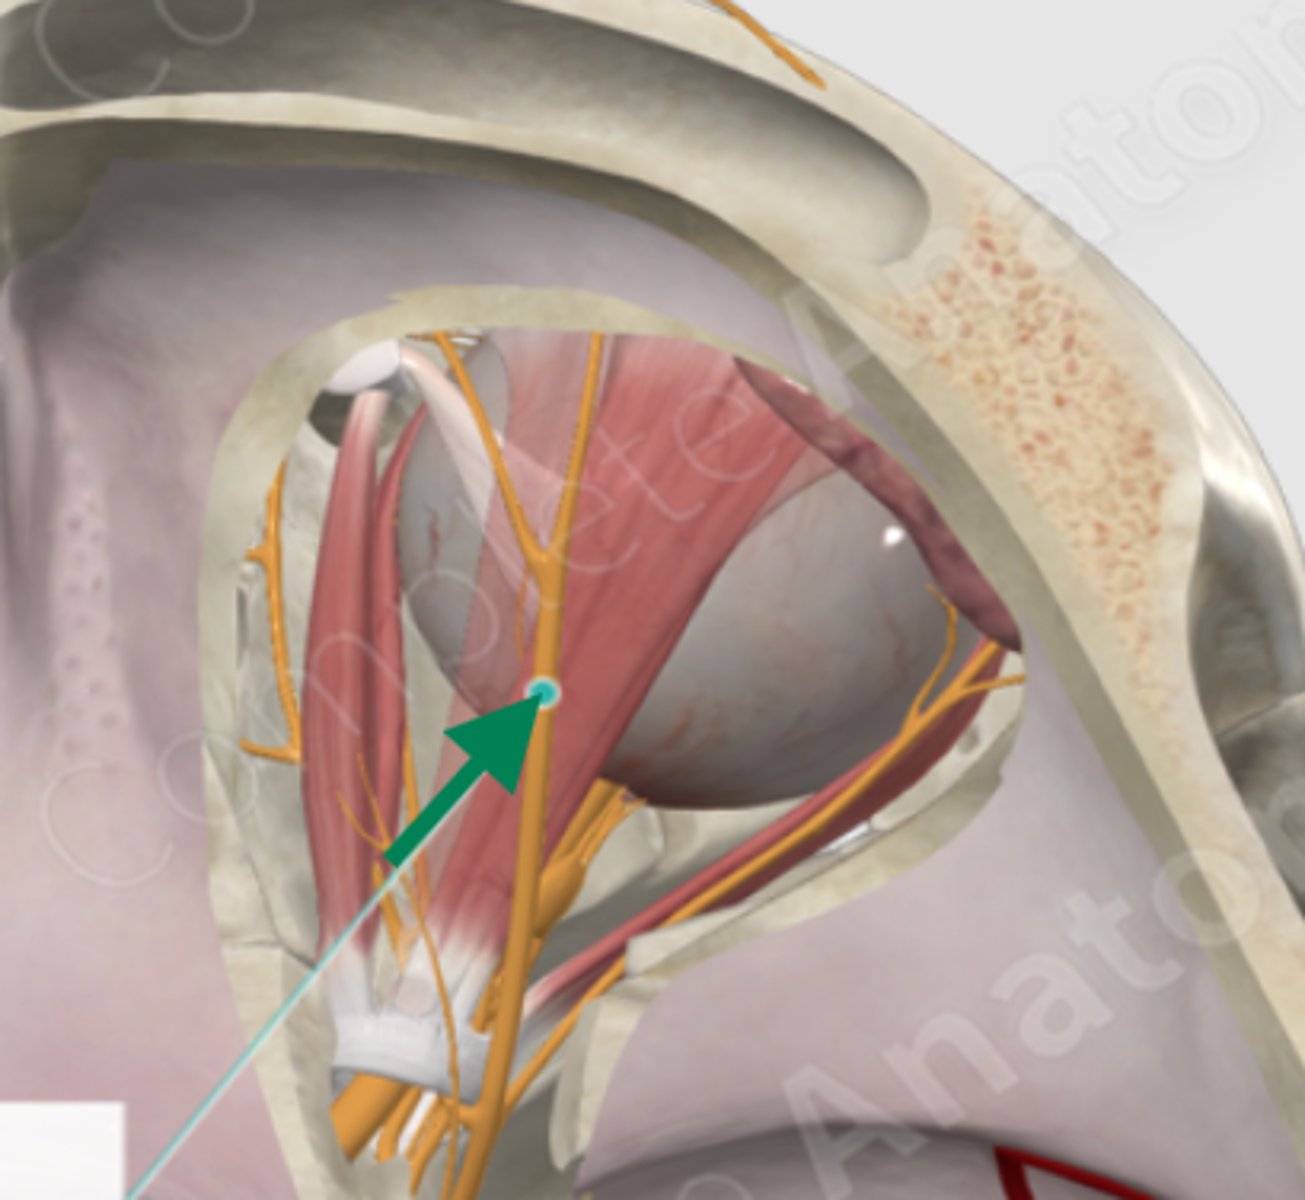

superior rectus

lateral rectus

superior oblique

superior oblique

superior rectus